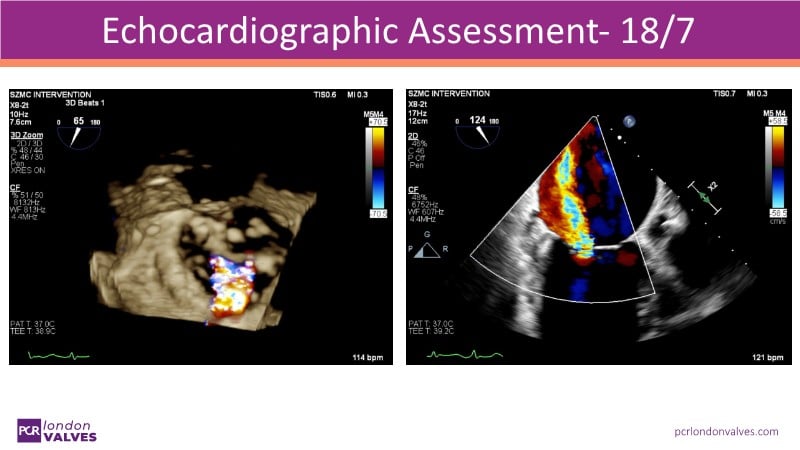

This LIVE case symposium brings mitral regurgitation guidelines into real clinical practice. Through step-by-step patient demonstrations and insightful discussion, the session explores how recommendations guide decision-making in ventricular and atrial secondary MR, how the heart team tailors therapy to individual anatomy and comorbidities, and how device iterations and procedural workflow can influence outcomes.